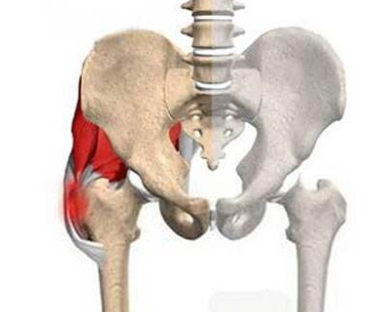

郑州治疗骨科医院讲解股骨头坏死髓腔减压术是什么?

郑州治疗骨科医院介绍到股骨头坏死常常是由于不良的生活习惯引起的,比如过度的饮酒,长期…[详情]